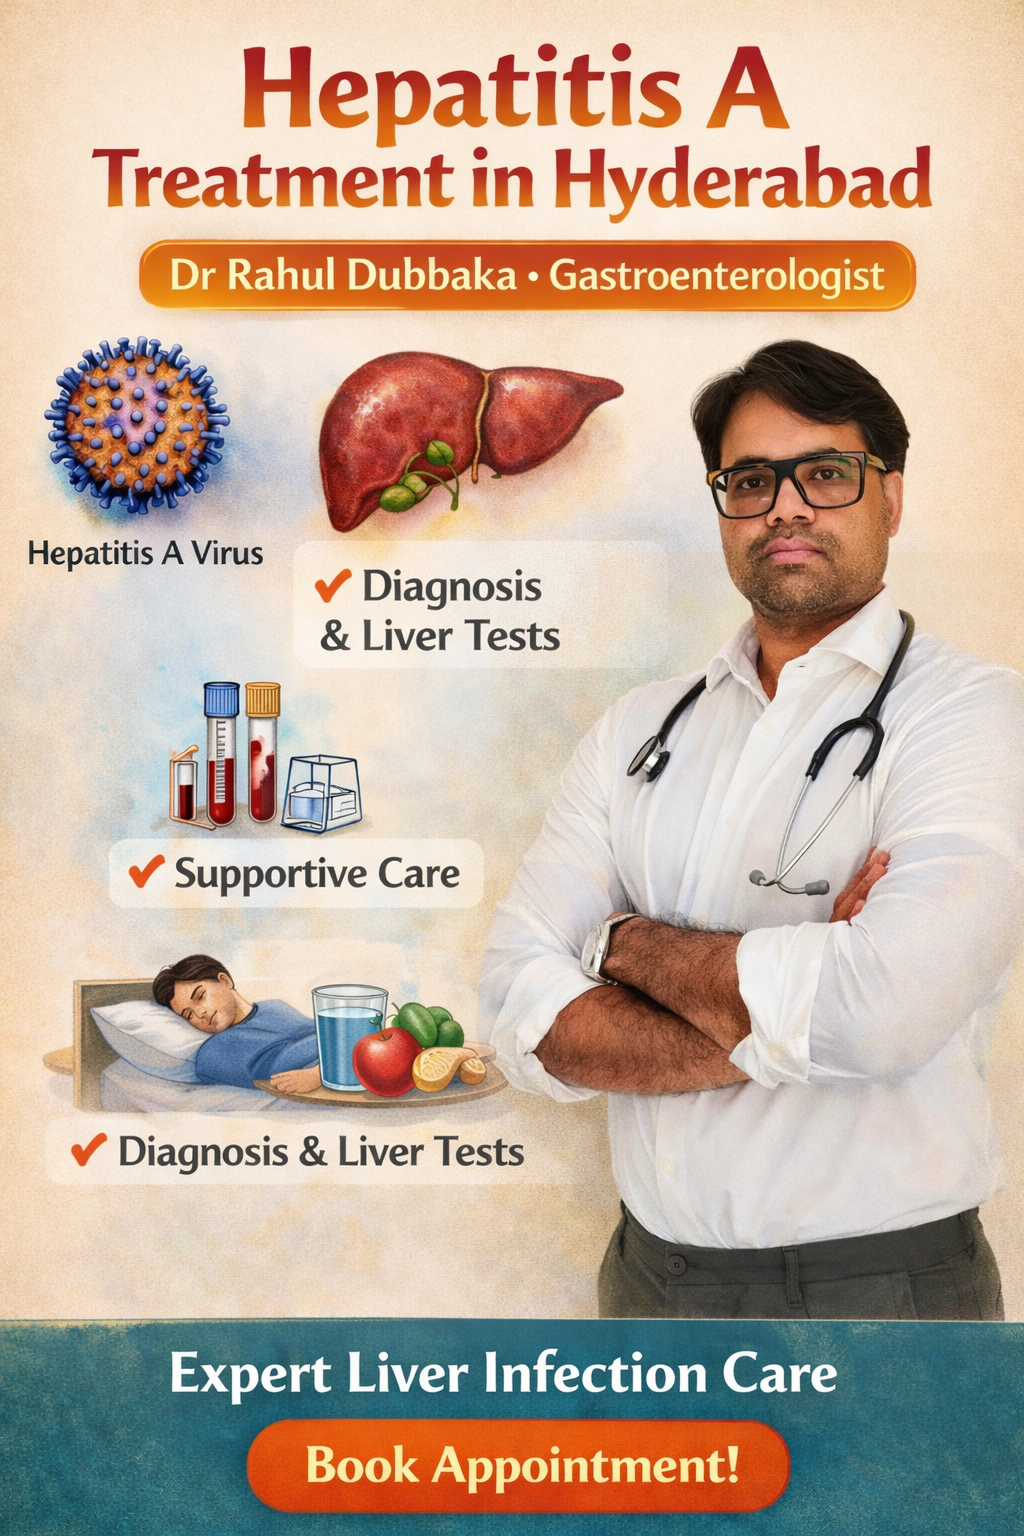

Hepatitis C Treatment in Hyderabad – Expert Care

Looking for Hepatitis C treatment in Hyderabad? Dr Rahul Dubbaka offers advanced antiviral therapy with 95%+ cure rates at People’s Hospital, Pragathi Nagar. Book your consultation today at +91 9100921514. Hepatitis C is a viral infection that primarily affects the liver and can silently damage it over time. If left untreated, it may lead to serious complications such as cirrhosis, liver failure, and even liver cancer. The good news is that with modern medical advancements, Hepatitis C is now highly curable with effective antiviral medications.

If you are searching for Hepatitis C Treatment in Hyderabad, consulting an experienced gastroenterologist and hepatologist like Dr Rahul Dubbaka can ensure accurate diagnosis, personalized treatment, and long-term liver health management.

Dr Rahul Dubbaka practices at People’s Hospital, offering advanced liver care services for patients across Hyderabad.

Why Choose Dr Rahul Dubbaka for Hepatitis C Treatment in Hyderabad?

Dr Rahul Dubbaka is a reputed gastroenterologist and liver specialist with expertise in managing chronic liver diseases.

Diagnosis of Hepatitis C

Accurate diagnosis is essential before starting treatment.

1. HCV Antibody Test

Detects exposure to the virus.

2. HCV RNA PCR Test

Confirms active infection and measures viral load.

3. Liver Function Tests (LFTs)

Assess liver inflammation and damage.

Lifestyle Tips During Treatment

To support liver recovery:

Avoid alcohol completely

Eat a balanced, liver-friendly diet

Maintain healthy weight

Exercise moderately

Avoid self-medication

Attend regular follow-ups

Book Your Hepatitis C Consultation Today

If you or a loved one has been diagnosed with Hepatitis C, consult Dr Rahul Dubbaka at People’s Hospital for expert evaluation and advanced treatment.